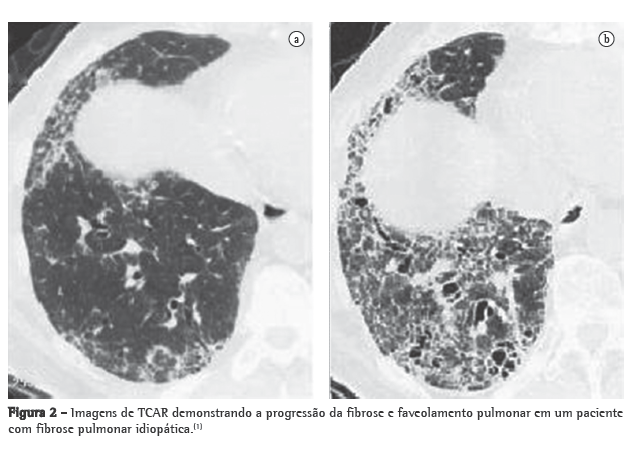

A TCAR do tórax é o melhor exame de imagem para a avaliação das DDPP. É útil na identificação da presença de doença, na avaliação de sua extensão e na caracterização de seu padrão. Também auxilia na restrição das opções de diagnósticos diferenciais, orienta o local de biópsia e avalia o curso clínico da doença e a resposta à terapia.(5) No entanto, devido à falta de especificidade diagnóstica, a TCAR não substitui a necessidade de confirmação histológica na maioria dos pacientes com DDPP(6) (Figura 2).